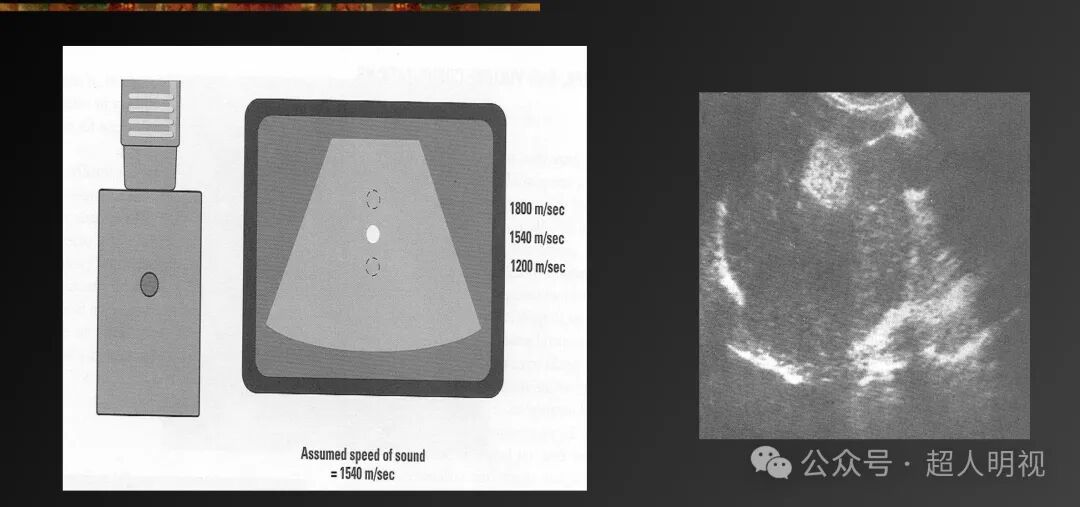

- 传播速度误差(声速偏离1540 m/s时,结构显示位置偏移)

- 声速>1540 m/s → 结构显示更近(回声返回更快)

- 声速<1540 m/s → 结构显示更远(回声返回更慢)

彩超伪像是什么超声伪像_https://www.jmylbn.com_新闻资讯_第9张